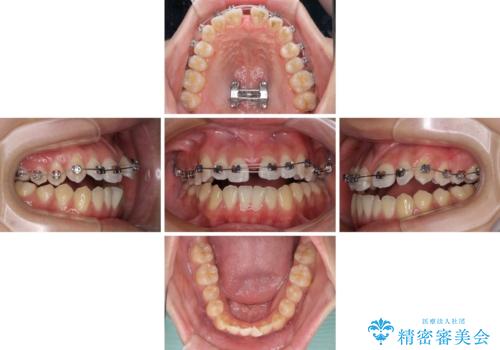

受け口と開咬を急速拡大装置とワイヤー装置で改善

- メタルブラケット

- 1年3ヶ月

上顎歯列が狭窄していたため、急速拡大装置により上顎骨を側方に拡大し、その後ワイヤー装置にて矯正治療を行うこととしました。

舌の突出癖が開咬の原因であったので、改善のための舌トレーニングを行っていただきました。

舌トレーニングは後戻りにも大きく影響するため、とても重要なトレーニングです。